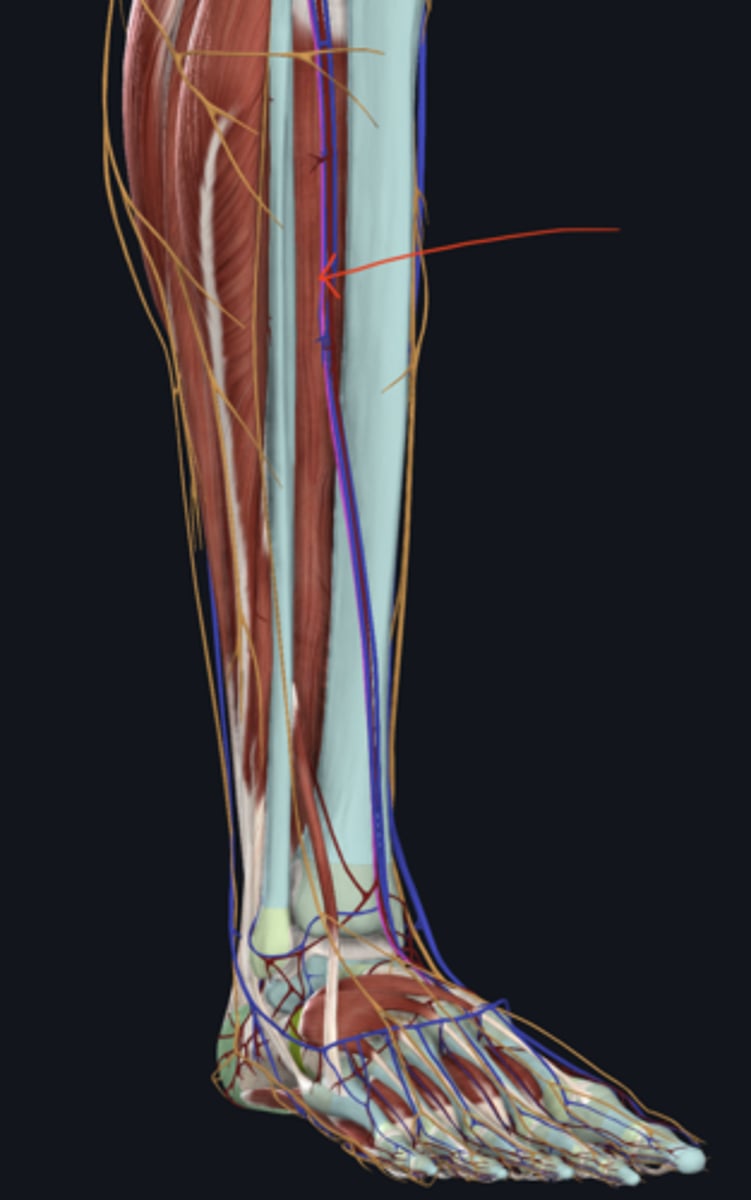

Anterior tibial artery

artery

Common fibular nerve

nerve highlighted in pink

Deep fibular nerve

nerve, deep

Superficial fibular nerve

nerve, superficial

Great saphenous vein

vein